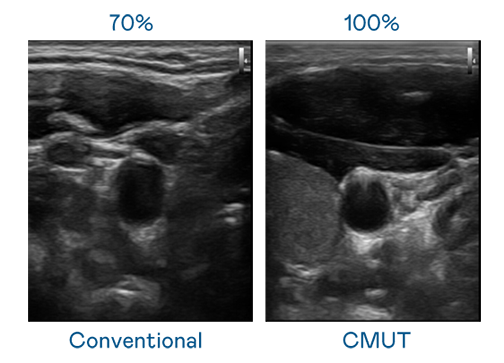

CMUT 技术是一种用电容式微机电元件来产生超音波讯号的技术。与传统 PZT 压电式技术相比,CMUT 频宽增加 30%,更宽频的超音波讯号让影像解析度大幅提升,是实现高影像品质医疗超音波扫描、促进精准医疗发展的关键技术。

大频宽带来超清晰影像

超音波影像的解析度高低,首先取决于探头能发出的讯号频宽。双鱼直播平台 CMUT 可提供高清晰的超音波讯号,提供高频宽、高灵敏度、影像纹理细节更高的超音波影像,协助医护人员缩短影像判读时间及利用精准的医疗影像进行诊断。